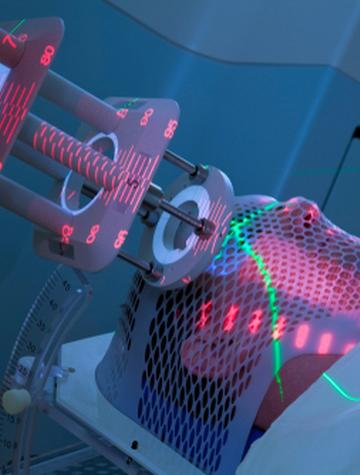

Cancer oligométastatique oligoprogressif : l’apport de la radiothérapie stéréotaxique corporelle

La radiothérapie stéréotaxique corporelle (RSC) consiste en une irradiation tumorale sélective guidée par l’imagerie en temps réel. Elle vise en règle des tumeurs primaires ou secondaires dont les dimensions n’excèdent pas 5 cm, le plus souvent isolées sans envahissement ganglionnaire. Elle permet de délivrer avec une précision millimétrique des rayons X de haute énergie sous la forme de mini-faisceaux multiples, généralement non coplanaires, des doses élevées fractionnées [...]